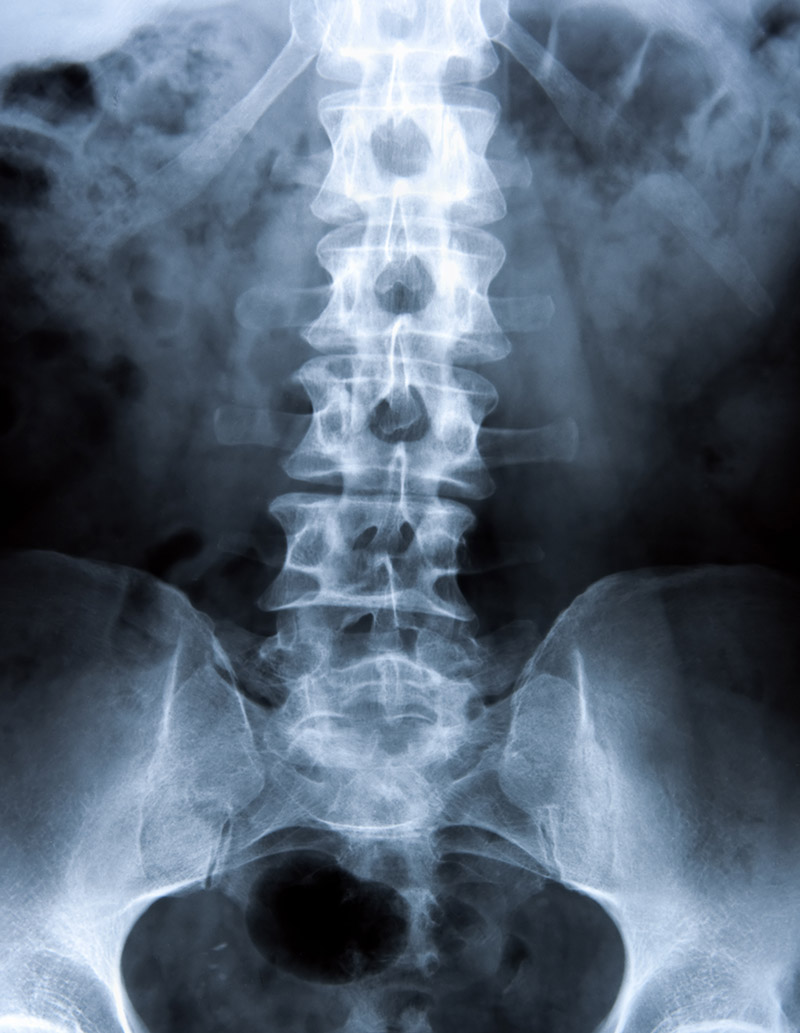

Spinal instability is a greater-than-normal range of motion between two vertebrae. Motion preservation surgery may be indicated for ligamental laxity but not for traumatic instability.